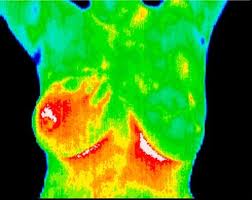

I’m using a thermographic image of Inflammatory Breast Cancer — so as not to be TOO graphic. Ever since one of my dear friends came down with IBC I’ve been aware that most of us women are NOT aware of it. The problem is that what we have learned about regular breast cancer doesn’t apply. There are No Lumps with IBC.